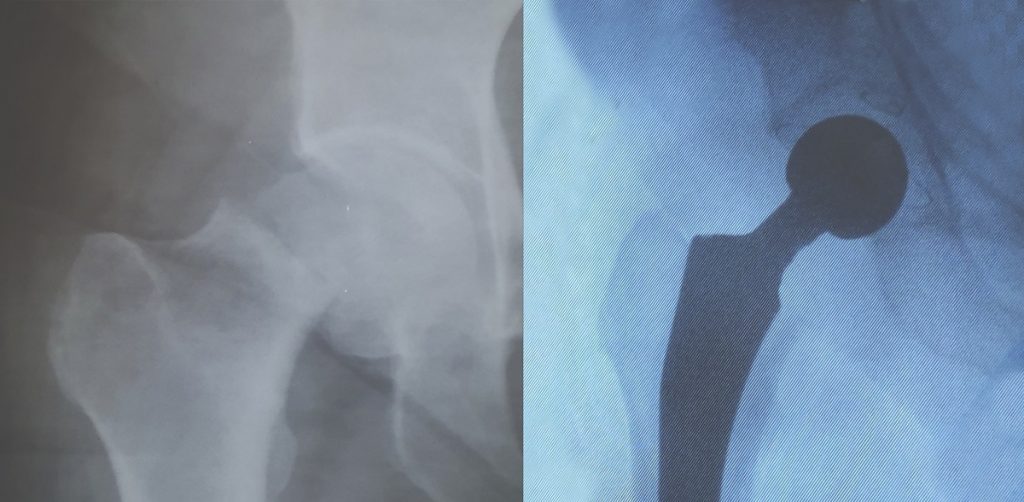

Запорожские ортопеды Межобластного центра восстановительной хирургии костей и суставов во главе с Игорем Руденко в кратчайший срок поставили на ноги пациентку с переломом шейки бедра. Это позволит ей уже через неделю продолжить лечение основного заболевания – рака молочной железы.

Благодаря многолетнему опыту, передовым методикам и современному оборудованию больной было выполнено эндопротезирование тазобедренного сустава. Также были иссечены ткани, пораженные метастазированием. Операция длилась около часа и прошла с минимальной кровопотерей — до 100 мл. Это, к слову, в четыре раза меньше, чем обычно сдает донор.

Уже на второй день после операции больная начала самостоятельно ходить. Внутрикожные швы позволяют ей безбоязненно находиться вне больничной палаты и специальных условий, призванных обеспечить асептичную безопасность. Сегодня она чувствует себя достаточно бодро и уверенно, чтобы продолжить лечение онкологического заболевания.